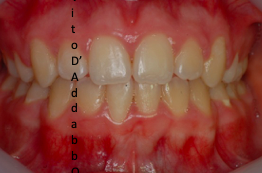

prima

dopo – fase 1